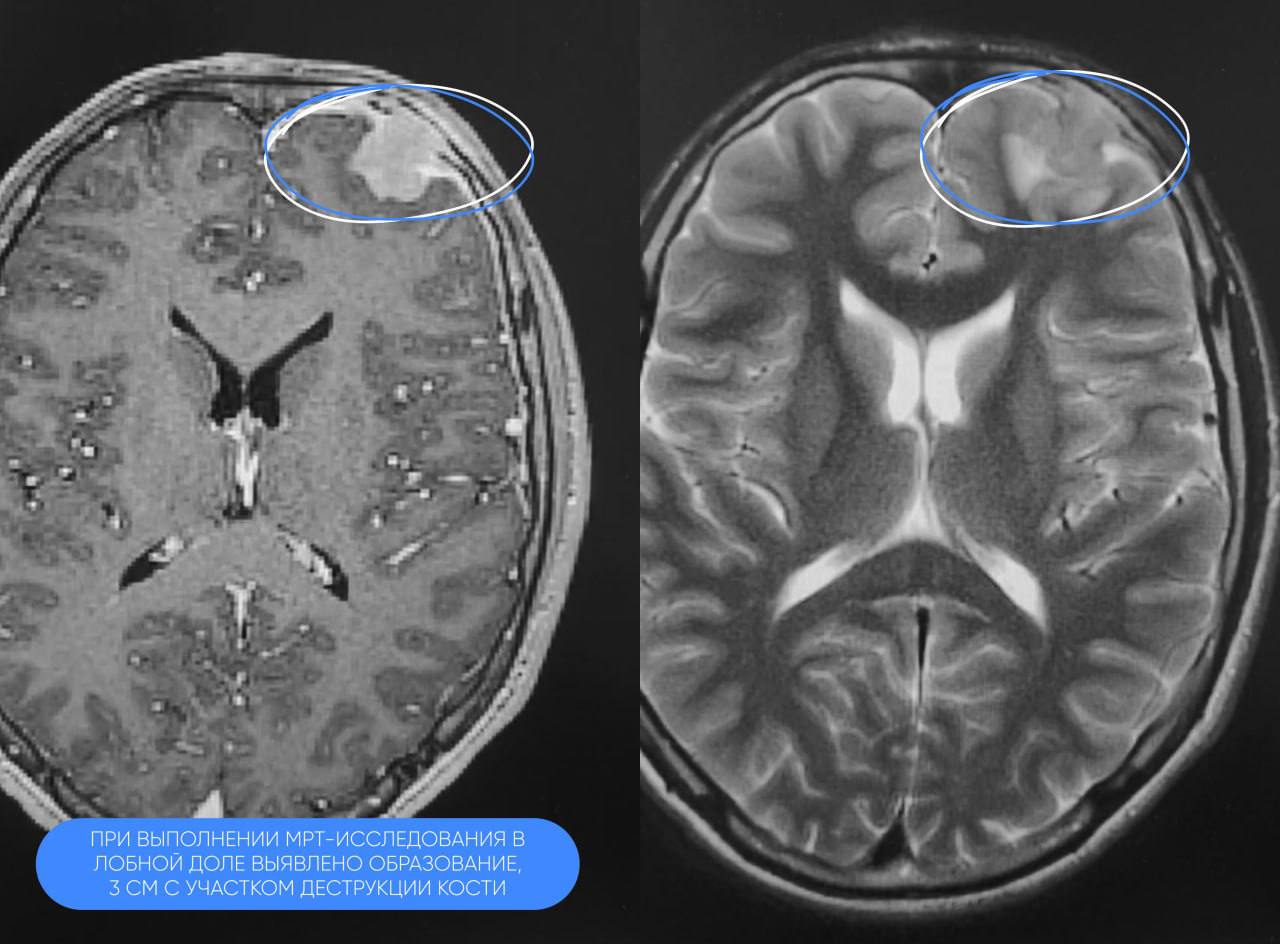

В травмцентр Сургута обратился 12-летний мальчик с жалобами на сильные головные боли и потерю сознания. МРТ выявила у него объемное образование до 3 см в лобной доле с вовлечением костной ткани свода черепа.

Патоморфологи СОКБ провели дополнительное исследование. Была обнаружена редкая доброкачественная опухоль головного мозга — ювенильная ксантогранулема.